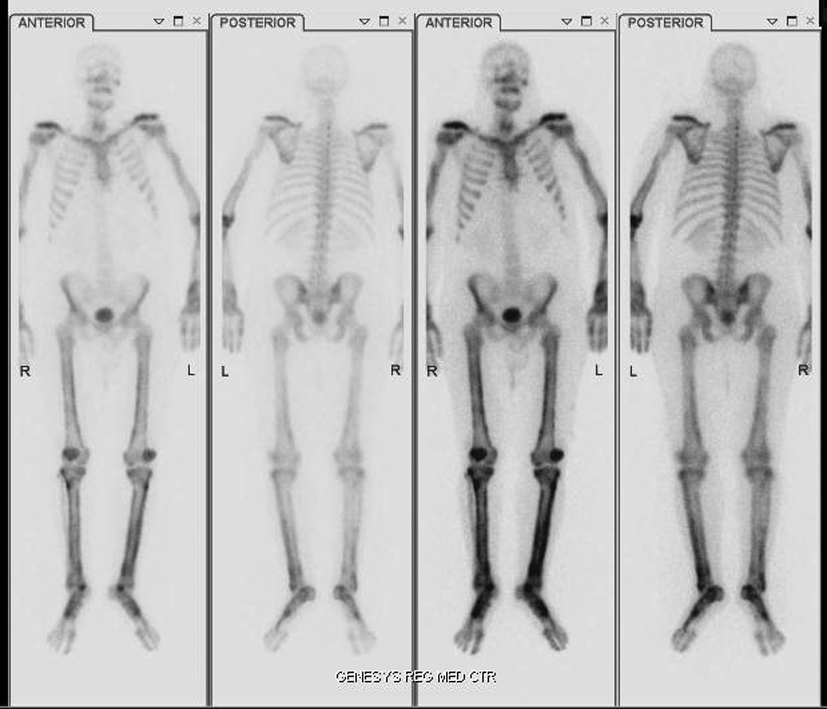

A 42 year old Caucasian male with no history of smoking and with a past medical history significant for hypertension and hypercholesterolemia presented to the emergency department (ED) with complaints of worsening shortness of breath over the past month. Upon further examination the patient complained of a 2 - 3 month history of bilateral upper and lower extremity pain, a 50 pound weight loss over 5 months, night sweats and persistent fever and chills. A computed tomography angiogram was ordered in the ED due to the suspicion of pulmonary embolism which was subsequently negative for pulmonary embolism (PE), but a 5.5 x 5.0 cm mass was noted in the left lower lobe that encased the bronchus and pulmonary artery (Fig. 1). Computed tomography (CT) guided biopsy was performed and the subsequent pathology report described findings consistent with sarcomatoid carcinoma. While awaiting pathology of the lung mass, further examination into the extremity pain was worked up and a bone scan was performed (Fig. 2) On bone scintigraphy there is increased peripheral periosteal and cortical uptake of technetium-99m MDP bilaterally in the femurs, tibias, clavicles and midfeet demonstrating the unique characteristics that are consistent with hypertrophic pulmonary osteoarthropathy secondary to the lung cancer. The patient underwent a pneumonectomy via muscle sparing thoracotomy and after recovering from ventilator dependent respiratory failure, secondary to acute respiratory distress syndrome, the patient began to demonstrate improvement in his symptoms. The pain in his legs started to subside and the patient is schedule to follow up in the clinic to begin chemotherapy.

![]() Click for large image | Figure 2. HPOA demonstrated on Bone Scan with increased peripheral periosteal and cortical uptake of technetium-99m MDP in the femoral and tibial bones bilaterally as well as clavicles and midfoot. |

Initial imaging is x-ray. Periosteal membrane thickening is the hallmark of HPO and can be visible on plain radiograph. Bone scintigraphy is a helpful imaging tool that can also be used. On bone scintigraphy there will be increased peripheral periosteal and cortical uptake of technetium-99m typically in the long bones.